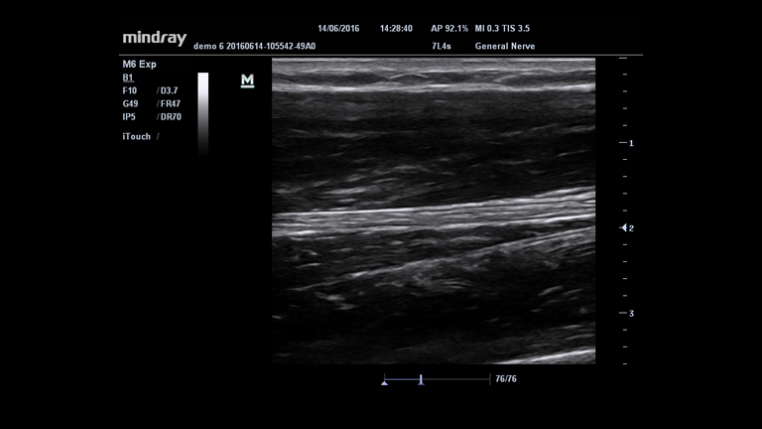

iBeam? (Toma de imágenes de composición espacial)